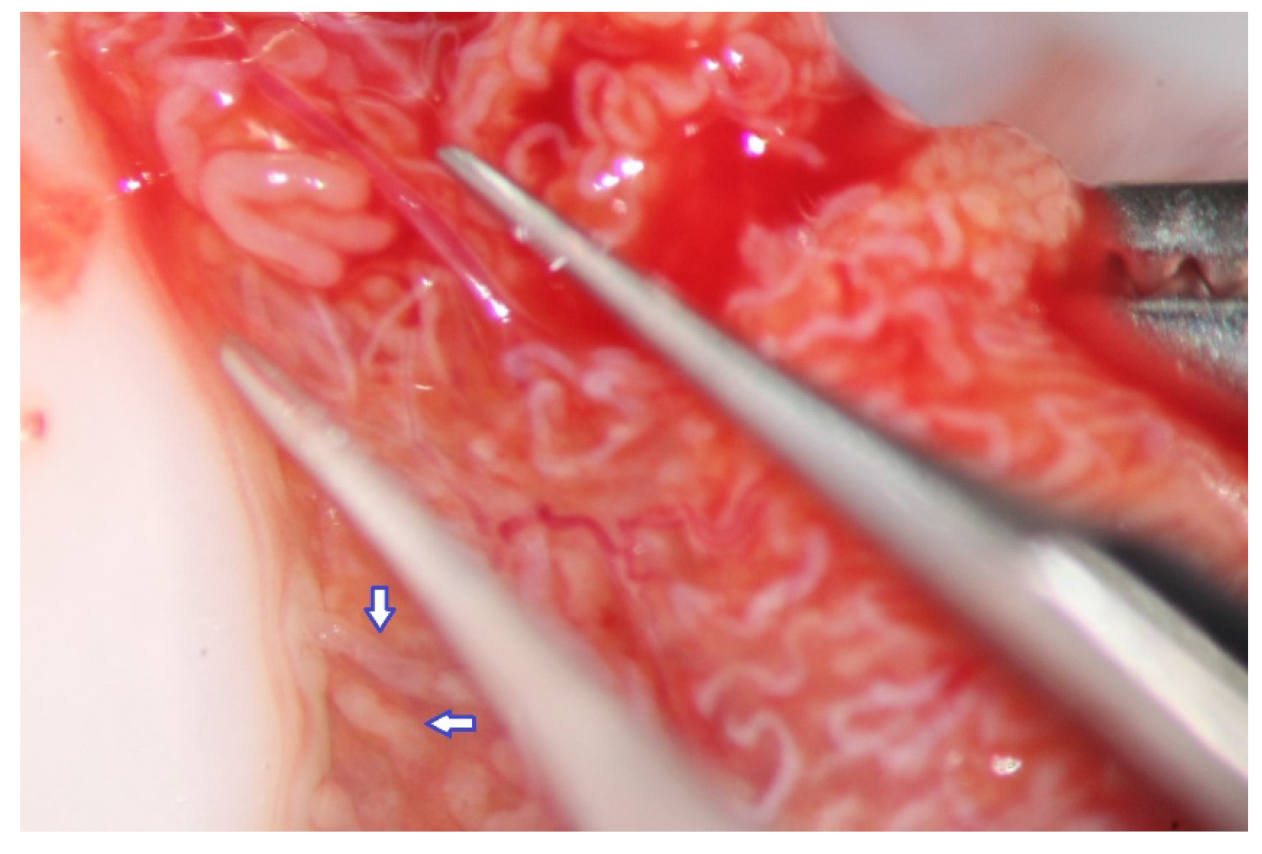

Figure 3. High magnification (×24- > ×36) allows the easy discrimination between seminiferous tubules of different sizes (those marked by blue arrows are very slightly larger than those marked by black arrows).

The evaluation of the testicular parenchyma at high magnification (×36) enables the surgeon to discriminate between STs that, at a lower magnification, may appear of comparable size (Figure 3).